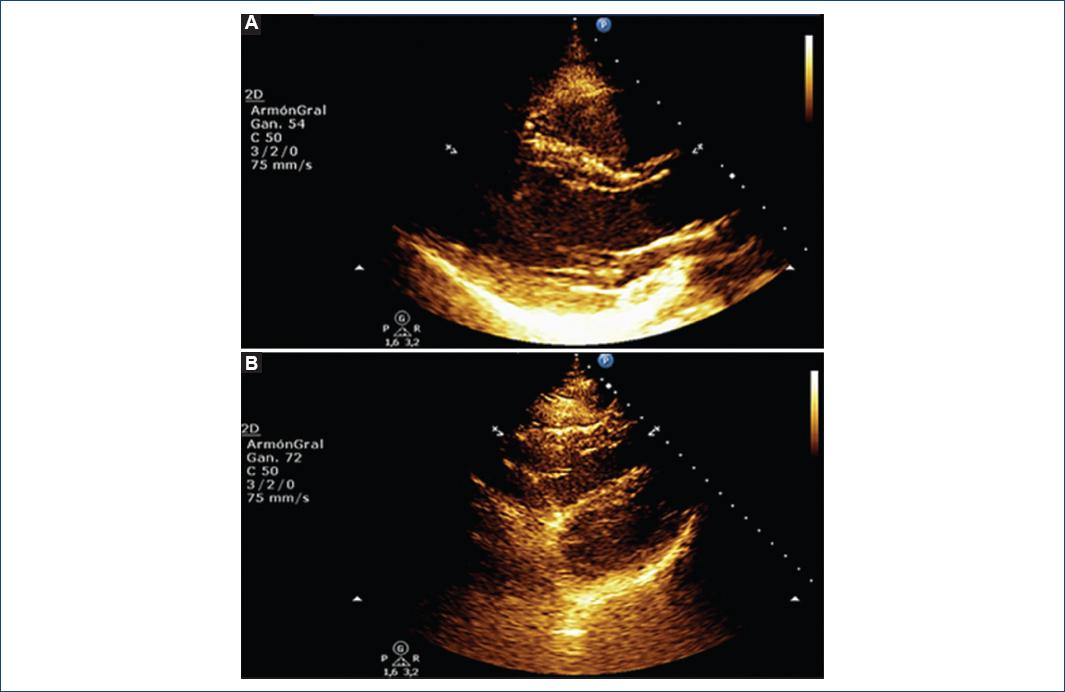

Se presenta el caso de una paciente de 33 años, sin antecedentes de relevancia, que consultó por aparición de fiebre, astenia, anosmia, ageusia y tos seca de 72 horas de evolución. Se obtuvo hisopado nasal para realizar reacción en cadena de la polimerasa para COVID-19, que resultó positivo. Se solicitó tomografía computarizada de tórax que descartó alteraciones del parénquima pulmonar y derrames pleural o pericárdico. Estudios de laboratorio: hematócrito, 38%; hemoglobina, 12 g/dl; leucocitos, 4,900 células/μl; plaquetas, 173,000/μl; y proteína C reactiva (PCR), 4.5 mg/l. Al sexto día del inicio de los síntomas presentó dolor torácico punzante que empeoraba con la inspiración profunda y mejoraba con el cambio del decúbito. La exploración física reveló frote sistólico y diastólico en posición de plegaria mahometana. El electrocardiograma (ECG) demostró taquicardia sinusal a 100 lpm, bloqueo incompleto de rama derecha, segmento ST infradesnivelado de 0.5 mV en DII, DIII, aVF, V5 y V6, y supradesnivelado cóncavo de 0.5 mV en V1 y V2 con T concordante. El análisis de laboratorio registró el nivel de troponina T ultrasensible < 14 ng/l y la creatinina fosfocinasa de 55 UI/l (VN 20/180), mientras que el resto de los parámetros fueron normales. El ecocardiograma transtorácico (ETT) mostró buena función biventricular con engrosamiento parietal sistólico conservado, marcada refringencia pericárdica posterior y ausencia de derrame pericárdico (Fig. 1A y 1B). Se interpretó el cuadro como pericarditis de probable causa viral por SARS-CoV-2, ya que se identificaron tres criterios diagnósticos de inflamación pericárdica en el contexto de dicha infección viral. Se inició ibuprofeno a dosis de 1,800 mg al día, con mejoría, y egresó del hospital a los siete días tras su ingreso.

Figura 1 Ecocardiogramas transtorácicos. A: eje largo paraesternal en el que se observa una marcada refringencia del pericardio en la cara posterior. B: vista subcostal de cuatro cámaras, con refringencia pericárdica en la cara lateral del ventrículo izquierdo.

La pericarditis aguda es un síndrome consecutivo a la inflamación pericárdica, con o sin derrame pericárdico adjunto, y sus causas más frecuentes son infecciones virales y las formas idiopáticas2. Su diagnóstico se establece si se satisfacen dos de cuatro criterios clínicos y siempre debe descartarse miocarditis adjunta mediante determinación de los marcadores de lesión miocárdica2. Cabe destacar que el hallazgo en este caso de hiperrefringencia del pericardio posterior o lateral puede ser un dato inespecífico debido a la mayor distancia de estas estructuras al transductor del ETT, por lo que siempre es fundamental evaluar el pericardio mediante tomografía computarizada de tórax. El tratamiento inicial es la administración de antiinflamatorios no esteroideos y colchicina para reducir la inflamación y el dolor torácico y prevenir la recurrencia, en tanto que los corticoides se reservan ante contraindicación o falta de respuesta al tratamiento inicial2. Los factores relacionados con peor evolución incluyen fiebre, evolución subaguda, derrame pericárdico grave o taponamiento cardíaco, y la falta de respuesta a los antiinflamatorios en los primeros siete días2.